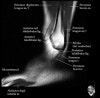

발목 관절의 MRI 단면 영상

- Sagittal section

Bones and marrow

Joint fluid

Talar dome

Subtalar joints

Achille's tendon

Sinus tarsi

Plantar fascia